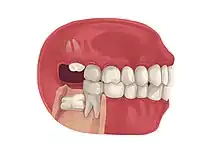

Impacted wisdom tooth

Wisdom teeth become impacted when there is not enough room in the jaws to allow for all of the teeth to erupt into the mouth. Because the wisdom teeth are the last to erupt, due to insufficient room in the jaws to accommodate more teeth, the wisdom teeth become stuck in the jaws, i.e., impacted. There is a genetic predisposition to tooth impaction. Genetics plays an important, albeit unpredictable role in dictating jaw and tooth size and tooth eruption potential of the teeth. Some also believe that there is an evolutionary decrease in jaw size due to softer modern diets that are more refined and less coarse than our ancestors'.[6]